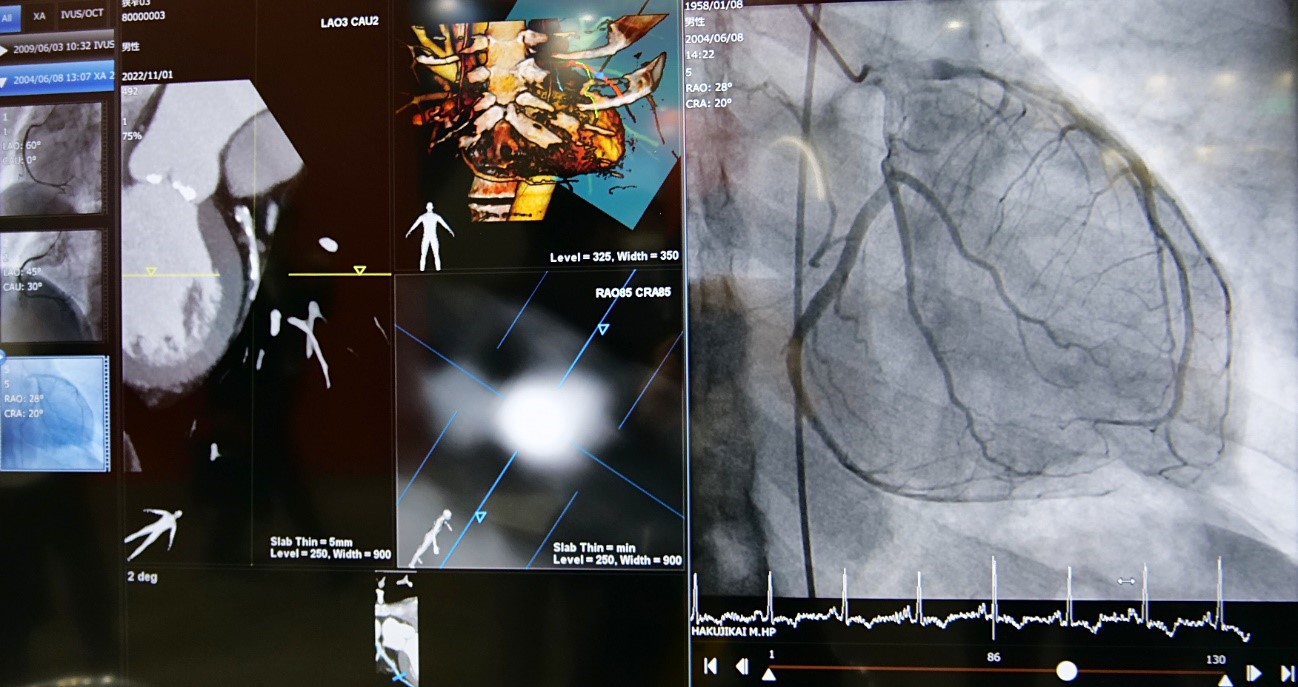

「Kada-View」は、Angio、IVUS、US、CTなどカテ室で必要な検査と治療のDICOM画像と動画像をオールインワンに表示するマルチモダリティビューワである。

今回新たに加わったCT Viewerオプションによって、術前CT画像を手技中に効率よく参照できるようになり、低侵襲で安全なPCIに一役買っている。なかでもリアルタイムに動作する「Sliding slab MIP」は、医師のクリックひとつで冠動脈近位部から遠位部までのCT長軸像・短軸像によるプラークの形状や性状の観察ができるようになった。手技中の治療戦略選択のストレスが軽減され、治療効率が大幅に向上する。